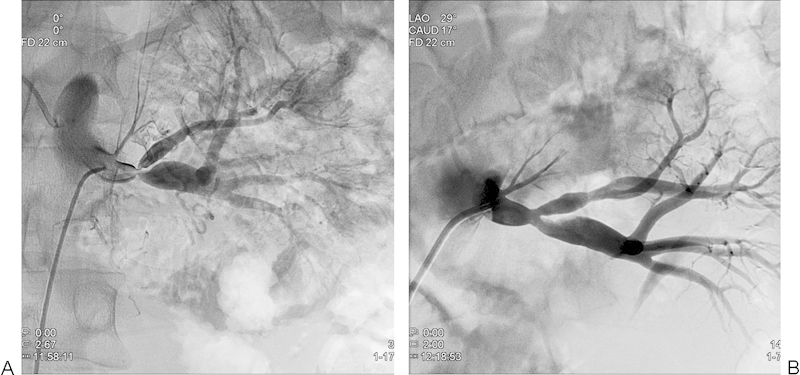

A 17-year-old patient newly diagnosed with arterial hypertension underwent magnetic resonance and dynamic scintigraphy of the kidneys. A single left renal artery stenosis was revealed (Fig. 2A). Renal angiogram was performed and confirmed a bifurcation stenosis of the left renal artery. Percutaneous transluminal angioplasty (PTA) of the stenotic lesion was successfully performed (Fig. 2B). Subsequently, during a 4-year follow-up, arterial hypertension was not demonstrated.

Fig. 2.

(A) An angiographic image of the left renal artery before PTA. The image reveals fibromuscular dysplasia of the left renal artery. The smooth focal stenosis is typical of intimal fibroplasia. (B) An angiographic image of the left renal artery after PTA. After PTA of severe stenosis, the left renal artery has a satisfactory appearance on angiography. PTA, percutaneous transluminal angioplasty.